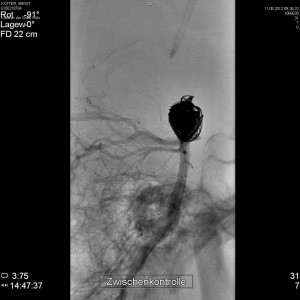

Am 11.08.2012 wurde das Aneurysma mittels des Coiling-Verfahren verfüllt: